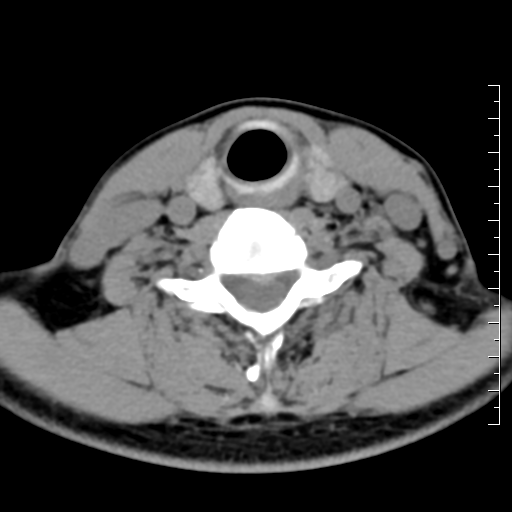

颈椎间盘ct